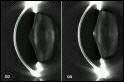

Pentacam: Die Pentacam vermisst mit Hilfe einer automatisch rotierenden Kamera den vorderen Augenabschnitt. Diese kontaktlose Messung dauert nur zwei Sekunden und erfasst die verschiedenen Ebenen des Auges durch 50 Aufnahmen. Fünf verschiedene Auswertungsmodule (Scheimpflugaufnahme, 3D-Kammeranalyse, Pachymetrie, Densitometrie und Hornhauttopographie) ermöglichen die differenzierte Auswertung der gewonnenen Daten. Mit der Kataraktanalyse kann man den Grad und das Fortschreiten einer Linsentrübung feststellen. Das Densitometriediagramm quantifiziert und dokumentiert den erkannten Schweregrad der Linsentrübung. Die Daten werden automatisch abgespeichert damit bei Folgemessungen der Krankheitsverlauf dokumentiert und exakt beurteilt werden kann. So wird der optimale Zeitpunkt für eine Staroperation gesichert.